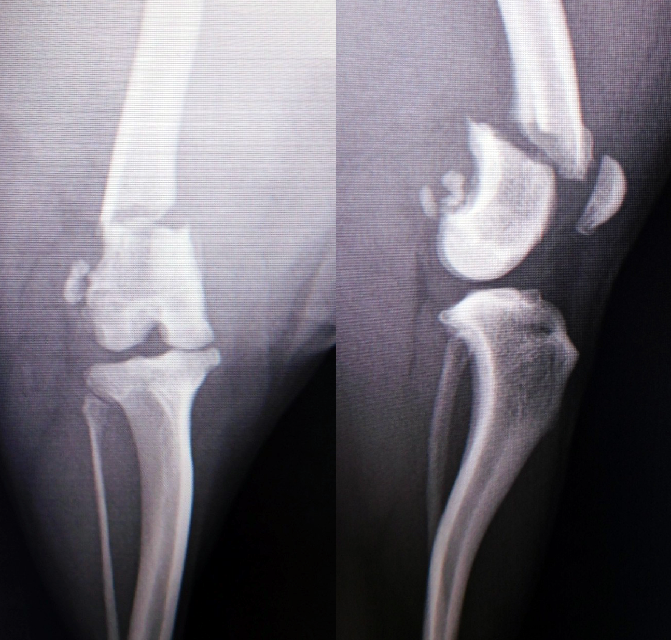

前十字靭帯断裂症

膝の前十字靭帯が外傷や加齢により完全断裂あるいは部分断裂により跛行がみられます。

小型犬から大型犬まで中高年で多く発症します。診断には整形外科検査とレントゲン検査が必要です。

断裂した前十字靭帯は再建できないため大腿骨と脛骨の位置関係を正常な状態に戻すことで膝関節の安定性を保つため脛骨高平部水平骨切り術(TPLO)と関節制動法(ラテラルスチャー法)があります。